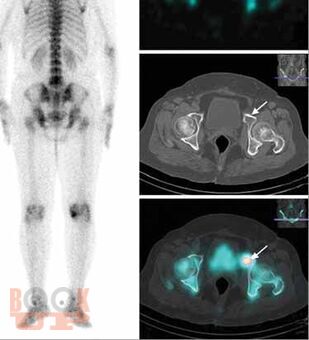

All chapters have been thoroughly revised. The present edition has incorporated 4 new chapters in the musculoskeletal subsections and 2 new chapters in the breast subsection. Content has been divided into 7 different subsections, beginning with current concepts and interventions. The first section deals with all imaging modalities in musculoskeletal imaging. There is an updated section on MR imaging, including new additions of imaging of wrist and ankle; peripheral nerve imaging and imaging of prosthetic joints. The second part of the book contains updated chapters on Breast imaging and interventions and includes two new chapters on Male Breast Imaging and Advances in Breast Imaging. This edition will serve as a concise yet comprehensive guide for students and practitioners of radiodiagnosis as well as a ready reckoner to clinicians in understanding the basics as well as current advances in imaging and interventions.